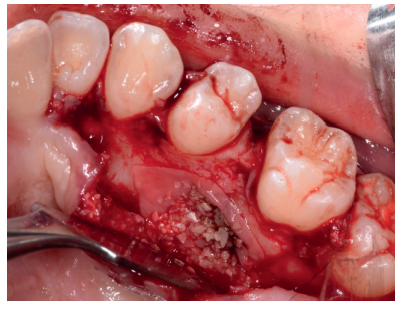

Tras el consentimiento informado, se realizó un bloqueo anestésico mediante Articaína al 4% con adrenalina 1: 100.000 del nervio dentario inferior y lingual, y posteriormente del nervio bucal. Se realizó una incisión festoneada lineal desde la cara distal del primer molar inferior izquierdo, hasta la cara distal del segundo molar inferior izquierdo, y se realizó una incisión oblicua hacia la rama ascendente mandibular. Tras el despegamiento mucoperióstico, se realizó una protección del nervio lingual durante las maniobras de ostectomía (Figura 5). Posteriormente, se realizó la ostectomía necesaria para liberar el límite amelocementario (LAC) del tercer molar inferior (Figura 6), procediendo a su luxación mediante botador recto, odontosección coronal con pieza de mano y fresa redonda de carburo de tungsteno (Figura 7), y exodoncia del fragmento radicular una vez retirado el fragmento coronal. El alveolo se lavó con suero fisiológico y se suturó la herida con seda de 4/0 (Figura 8).

Una vez suturada la herida, se procedió a la extracción del premolar retenido en posición 2.5, para lo cual, tras el bloqueo anestésico de los nervios alveolares superiores posterior, medio y anterior y del nasopalatino y palatino mayor, se realizó una incisión festoneada lineal en la mucosa palatina, y un despegamiento mucoperióstico desde distal del primer molar superior izquierdo hasta distal del incisivo lateral superior izquierdo (Figura 9). Tras el despegamiento, se realizaron las maniobras de ostectomía con pieza de mano y fresa de carburo de tungsteno, la odontosección coronal, y la exodoncia del fragmento coronal y radicular (Figura 10). Al observar la cavidad resultante (Figura 11), se apreció una perforación en la membrana del seno maxilar (Figura 12), en la que se colocó una membrana reabsorbible de colágeno (XFina, Osteógenos®, Madrid, España), de manera previa a la colocación del injerto de dentina (Figura 13). Se le hizo morder al paciente una gasa estéril empapada en clorhexidina al 0,12%, durante la preparación del material de injerto.

Los fragmentos coronal y radicular procedentes del tercer molar inferior y del premolar superior se limpiaron de restos de tejidos blandos y, secos, se introdujeron en la máquina Smart Dentin Grinder® (Kometa Bio, BIONER, España), tal y como aparece en la Figura 14. Tras un ciclo de triturado de 3 segundos, y otro de tamizado de 20 segundos, el material obtenido se limpió con la primera solución durante 12 minutos, y después durante 3 minutos con la segunda solución (Figura 15), para después transportar el material de injerto al alveolo, con presión controlada (Figura 16). Una vez compactado, se colocó una membrana de colágeno (Figura 17) y se suturó la herida con seda de 4/0, mediante puntos periodontales en las papilas (Figura 18). Se realizó una radiografía panorámica en el postoperatorio inmediato (Figura 19).